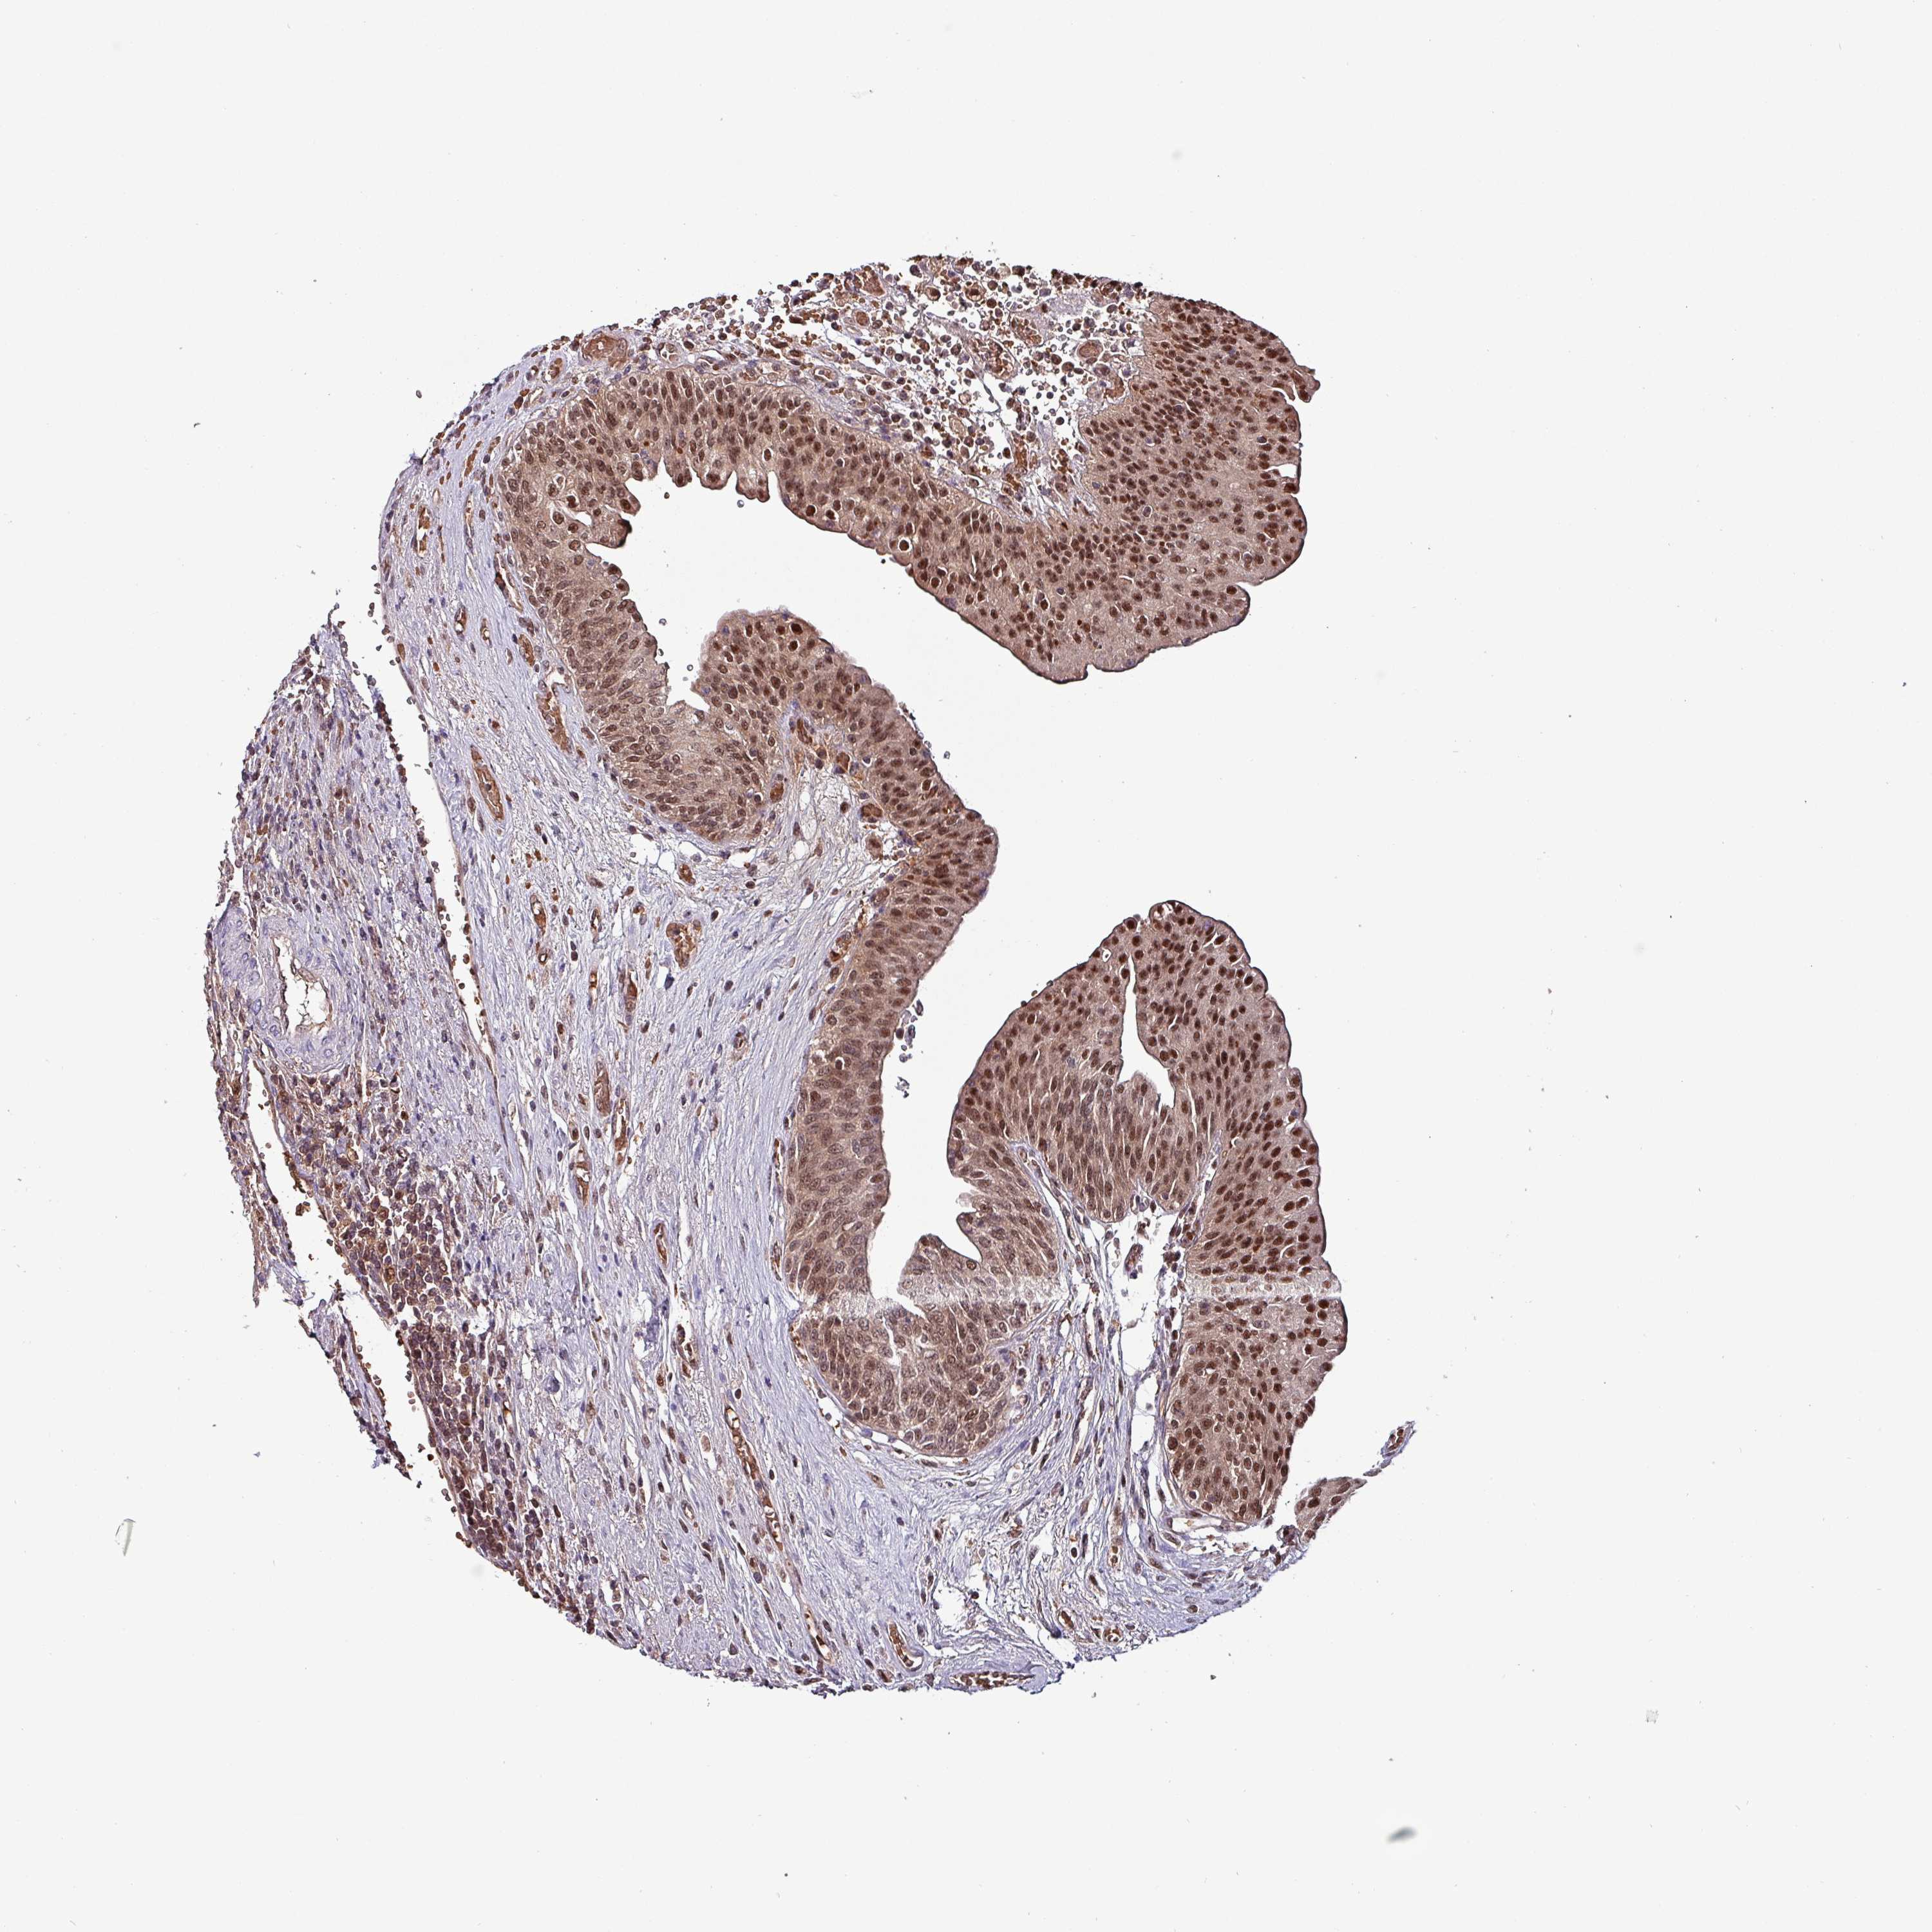

UROTHELIAL CANCER - Protein expressioni

A mouse-over function shows sample information and annotation data. Click on an image to view it in a full screen mode. Samples can be filtered based on level of antibody staining by selecting one or several of the following categories: high, medium, low and not detected. The assay and annotation is described here.

Antibody stainingi

Antibody staining in the annotated cell types in the current human tissue is reported as not detected, low, medium, or high, based on conventional immunohistochemistry profiling in selected tissues. This score is based on the combination of the staining intensity and fraction of stained cells.

Each image is clickable and will lead to virtual microscopy that enables deeper exploration of all samples and also displays staining intensity scores, fraction scores and subcellular localization as well as patient and tissue information for each sample.

Antibody HPA046995

Antibody HPA050327

Urothelial carcinoma, High grade

Urothelial carcinoma, Low grade

Urothelial carcinoma, NOS